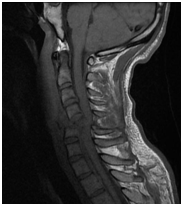

Anatómiai nyaki gerinc, láthatóvá MRI.

MRI lehetővé teszi, hogy megjelenítsék morfológiai változások: a csigolyatestek, porckorongok, gerincvelő, dura térben, az ideg gyökerek környező paravertebralis lágyrész, érrendszeri szerkezetek, amelyek a kutatási területen.

Jobb-paramedián, foraminalis porckorongsérv C6-C7.